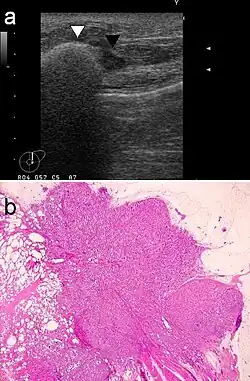

Die Diagnose eines Silikonoms oder Paraffinoms der Brust ist ausgesprochen schwierig. In vielen Fällen wird in der Erstdiagnose ein Karzinom vermutet, das ein sehr ähnliches Erscheinungsbild hat. Die sehr geringe Häufigkeit der Erkrankung und die im Vergleich dazu wesentlich höhere Häufigkeit von Brustkrebs sind für die Differentialdiagnose erschwerend. Auch die Anamnese ist in vielen Fällen keine Hilfe für die Diagnosestellung, da die meisten Patientinnen Jahrzehnte nach der Injektion des Paraffins beziehungsweise Silikons keinen kausalen Zusammenhang mehr zwischen Injektion und Erkrankung sehen. Von den bildgebenden Verfahren ist die Magnetresonanztomographie (MRT) der Sonografie und der Mammografie überlegen und ermöglicht die Unterscheidung zwischen maligner Neoplasie (Brustkrebs) und Lipogranulom.[30] Die MRT liefert zudem wichtige Informationen für die Planung des operativen Eingriffes und die notwendige vollständige Entfernung des Lipogranuloms.[31]

Diagnostische Sicherheit kann eine Biopsie gewährleisten, da erhebliche histologische Unterschiede zwischen Lipogranulom und Karzinom bestehen.